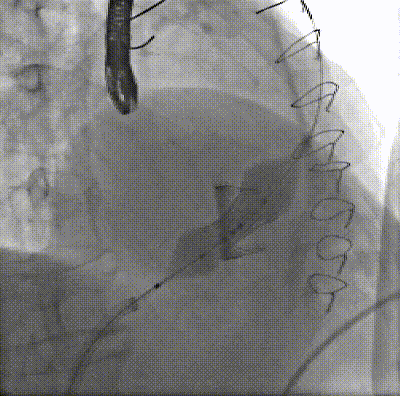

借助外科瓣顯影瓣架及輸送系統(tǒng)的顯影點進行球擴瓣的精準定位,由于是右心系統(tǒng),本身壓力低于50mmHg,故無需進行快速起搏。緩慢充盈球囊至完全釋放瓣膜,最終借助球擴瓣釋放過程的同軸自調(diào)整,完成瓣膜的釋放。

▲充盈球囊釋放瓣膜

釋放后瓣膜位置可再次充盈球囊進行后擴張。術中超聲顯示,瓣周及瓣中無反流。手術結束,撤除導管、導絲,拔除鞘管、縫合右股靜脈,壓迫止血?;颊呷樘K醒后返回CCU,術后生命體征穩(wěn)定。